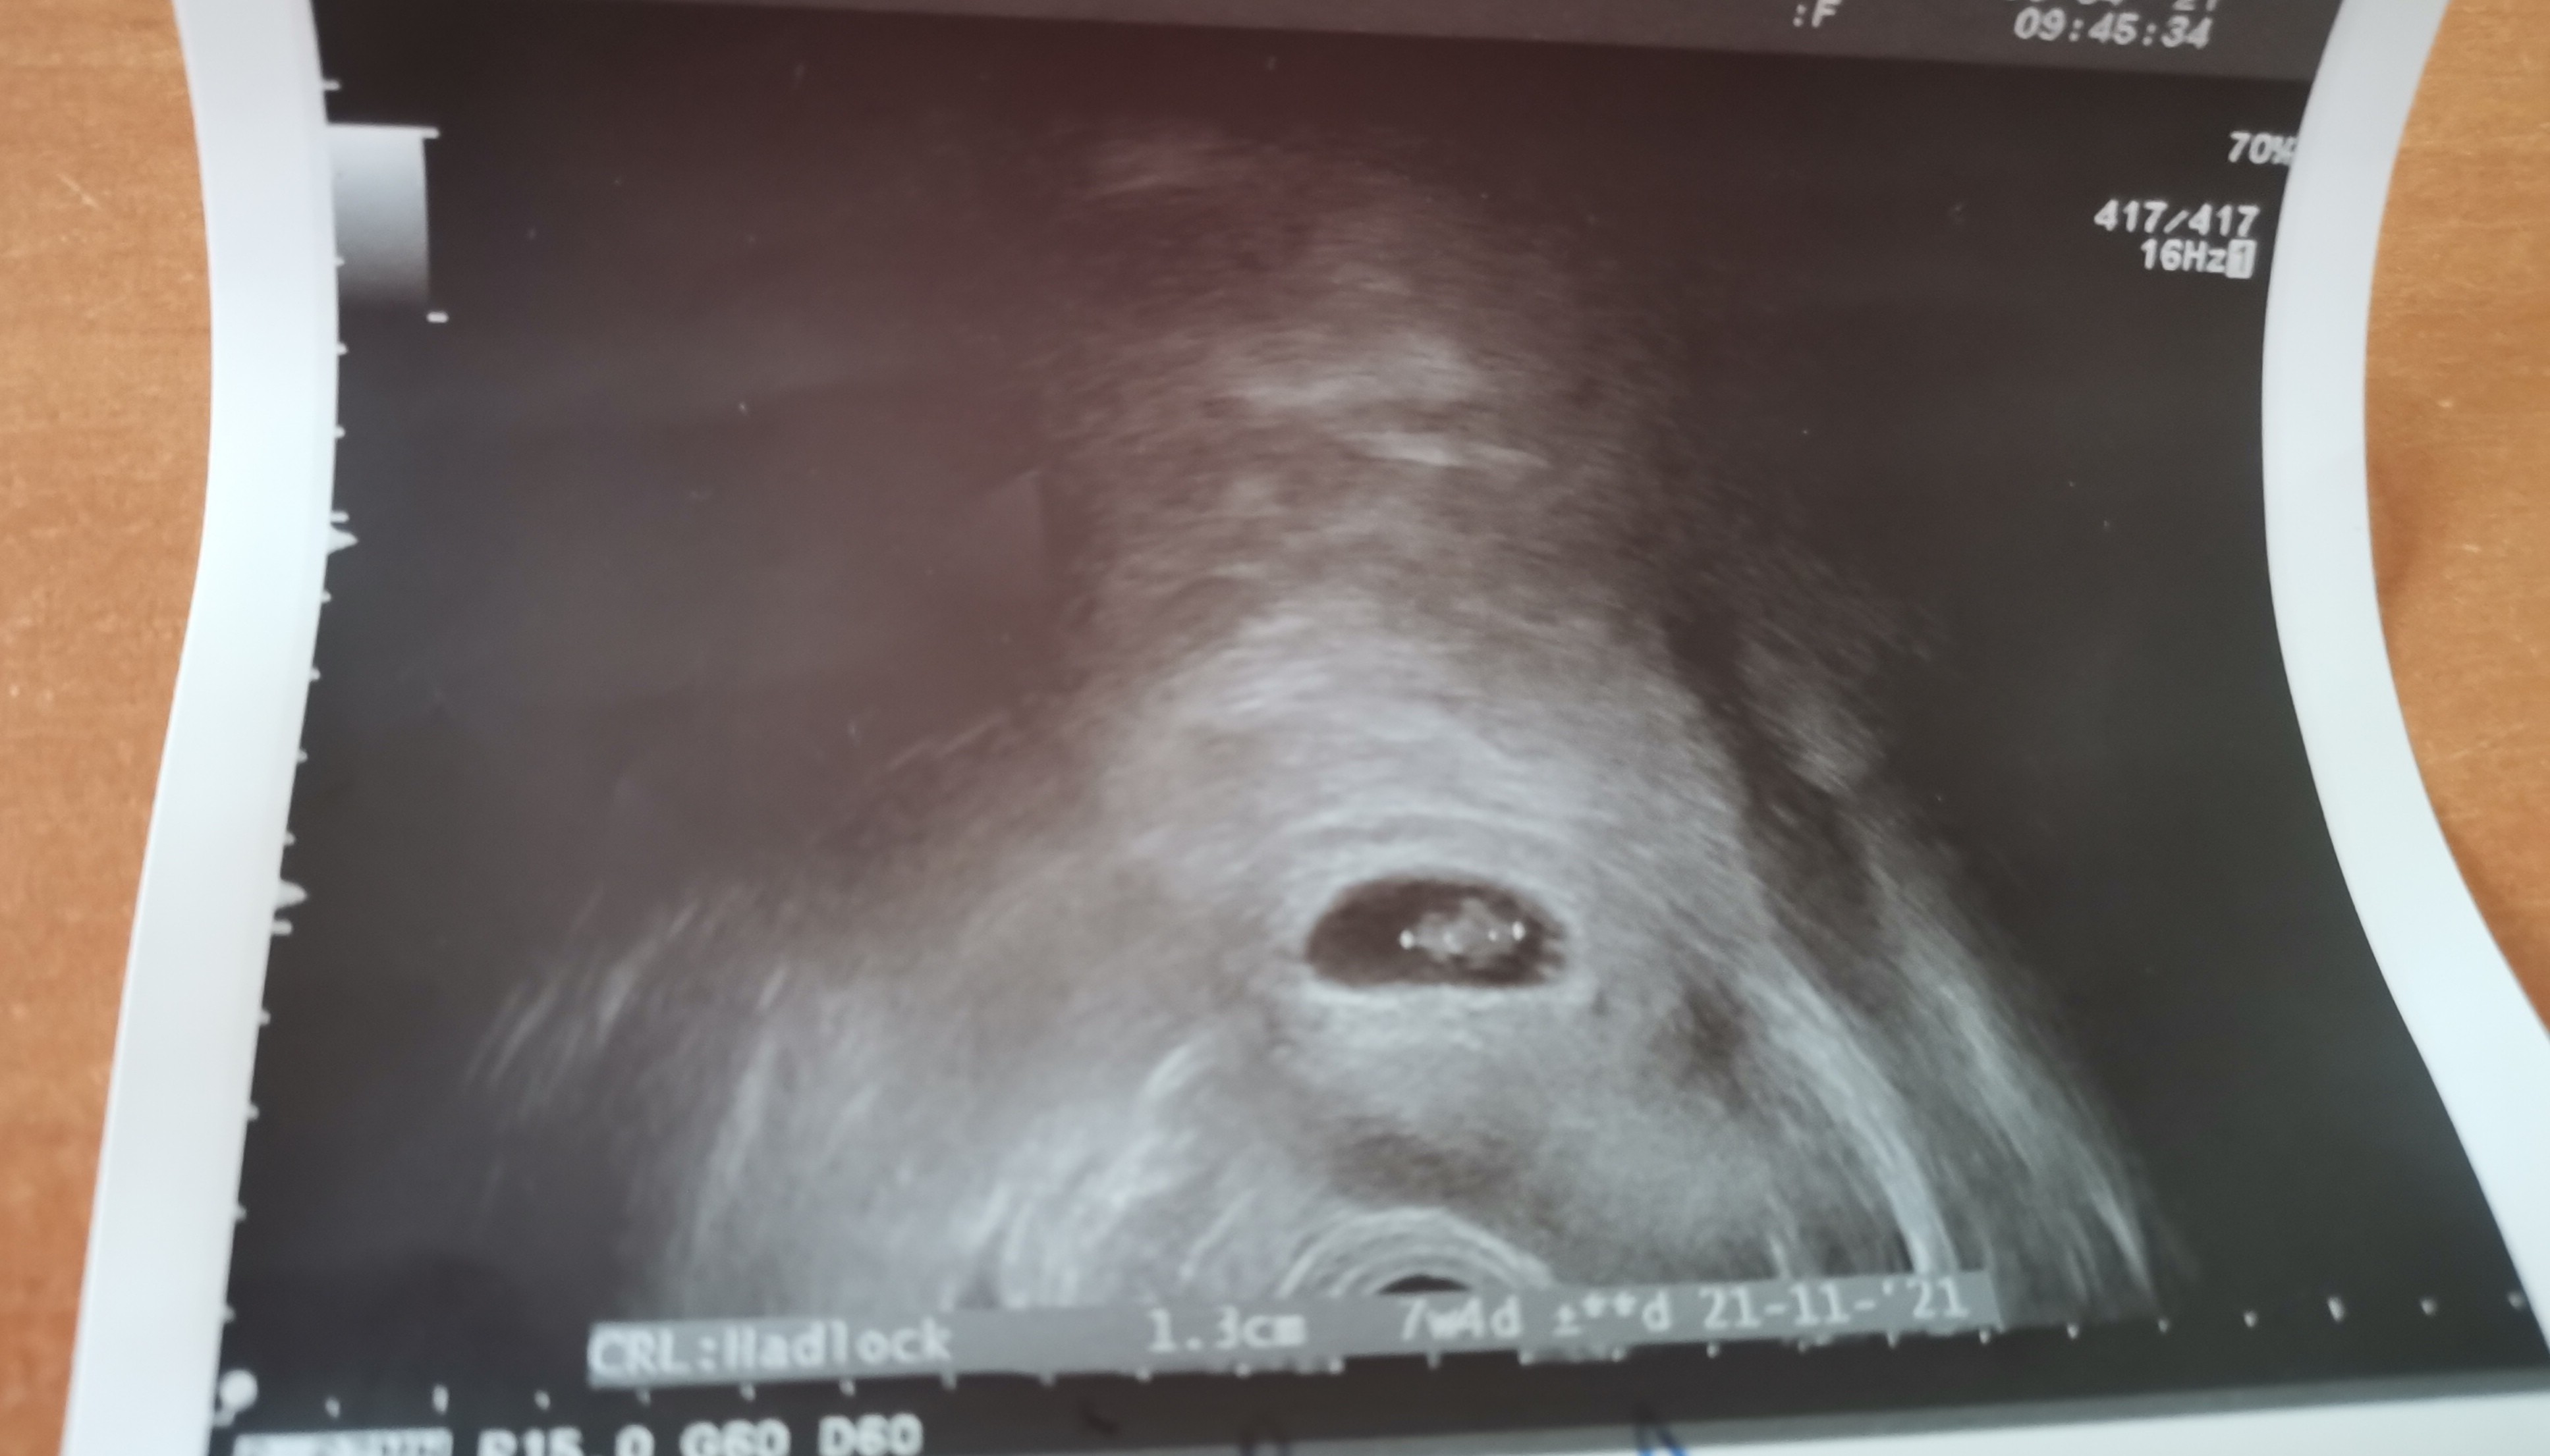

No i tak to wyglada. Sprzęt słaby, jestem gruba i niby jest ok ale dalej nie wiadomo 😂 dziś będę wydzwaniać do przychodni i zmieniać lekarza na tego do którego chodziłam w poprzedniej ciąży. Oby się udało bo przy pandemi może być ciężko 🙄

Załączniki

• IMG_20210408_110023.jpg

IMG_20210408_110023.jpg

706,4 KB · Wyświetleń: 150